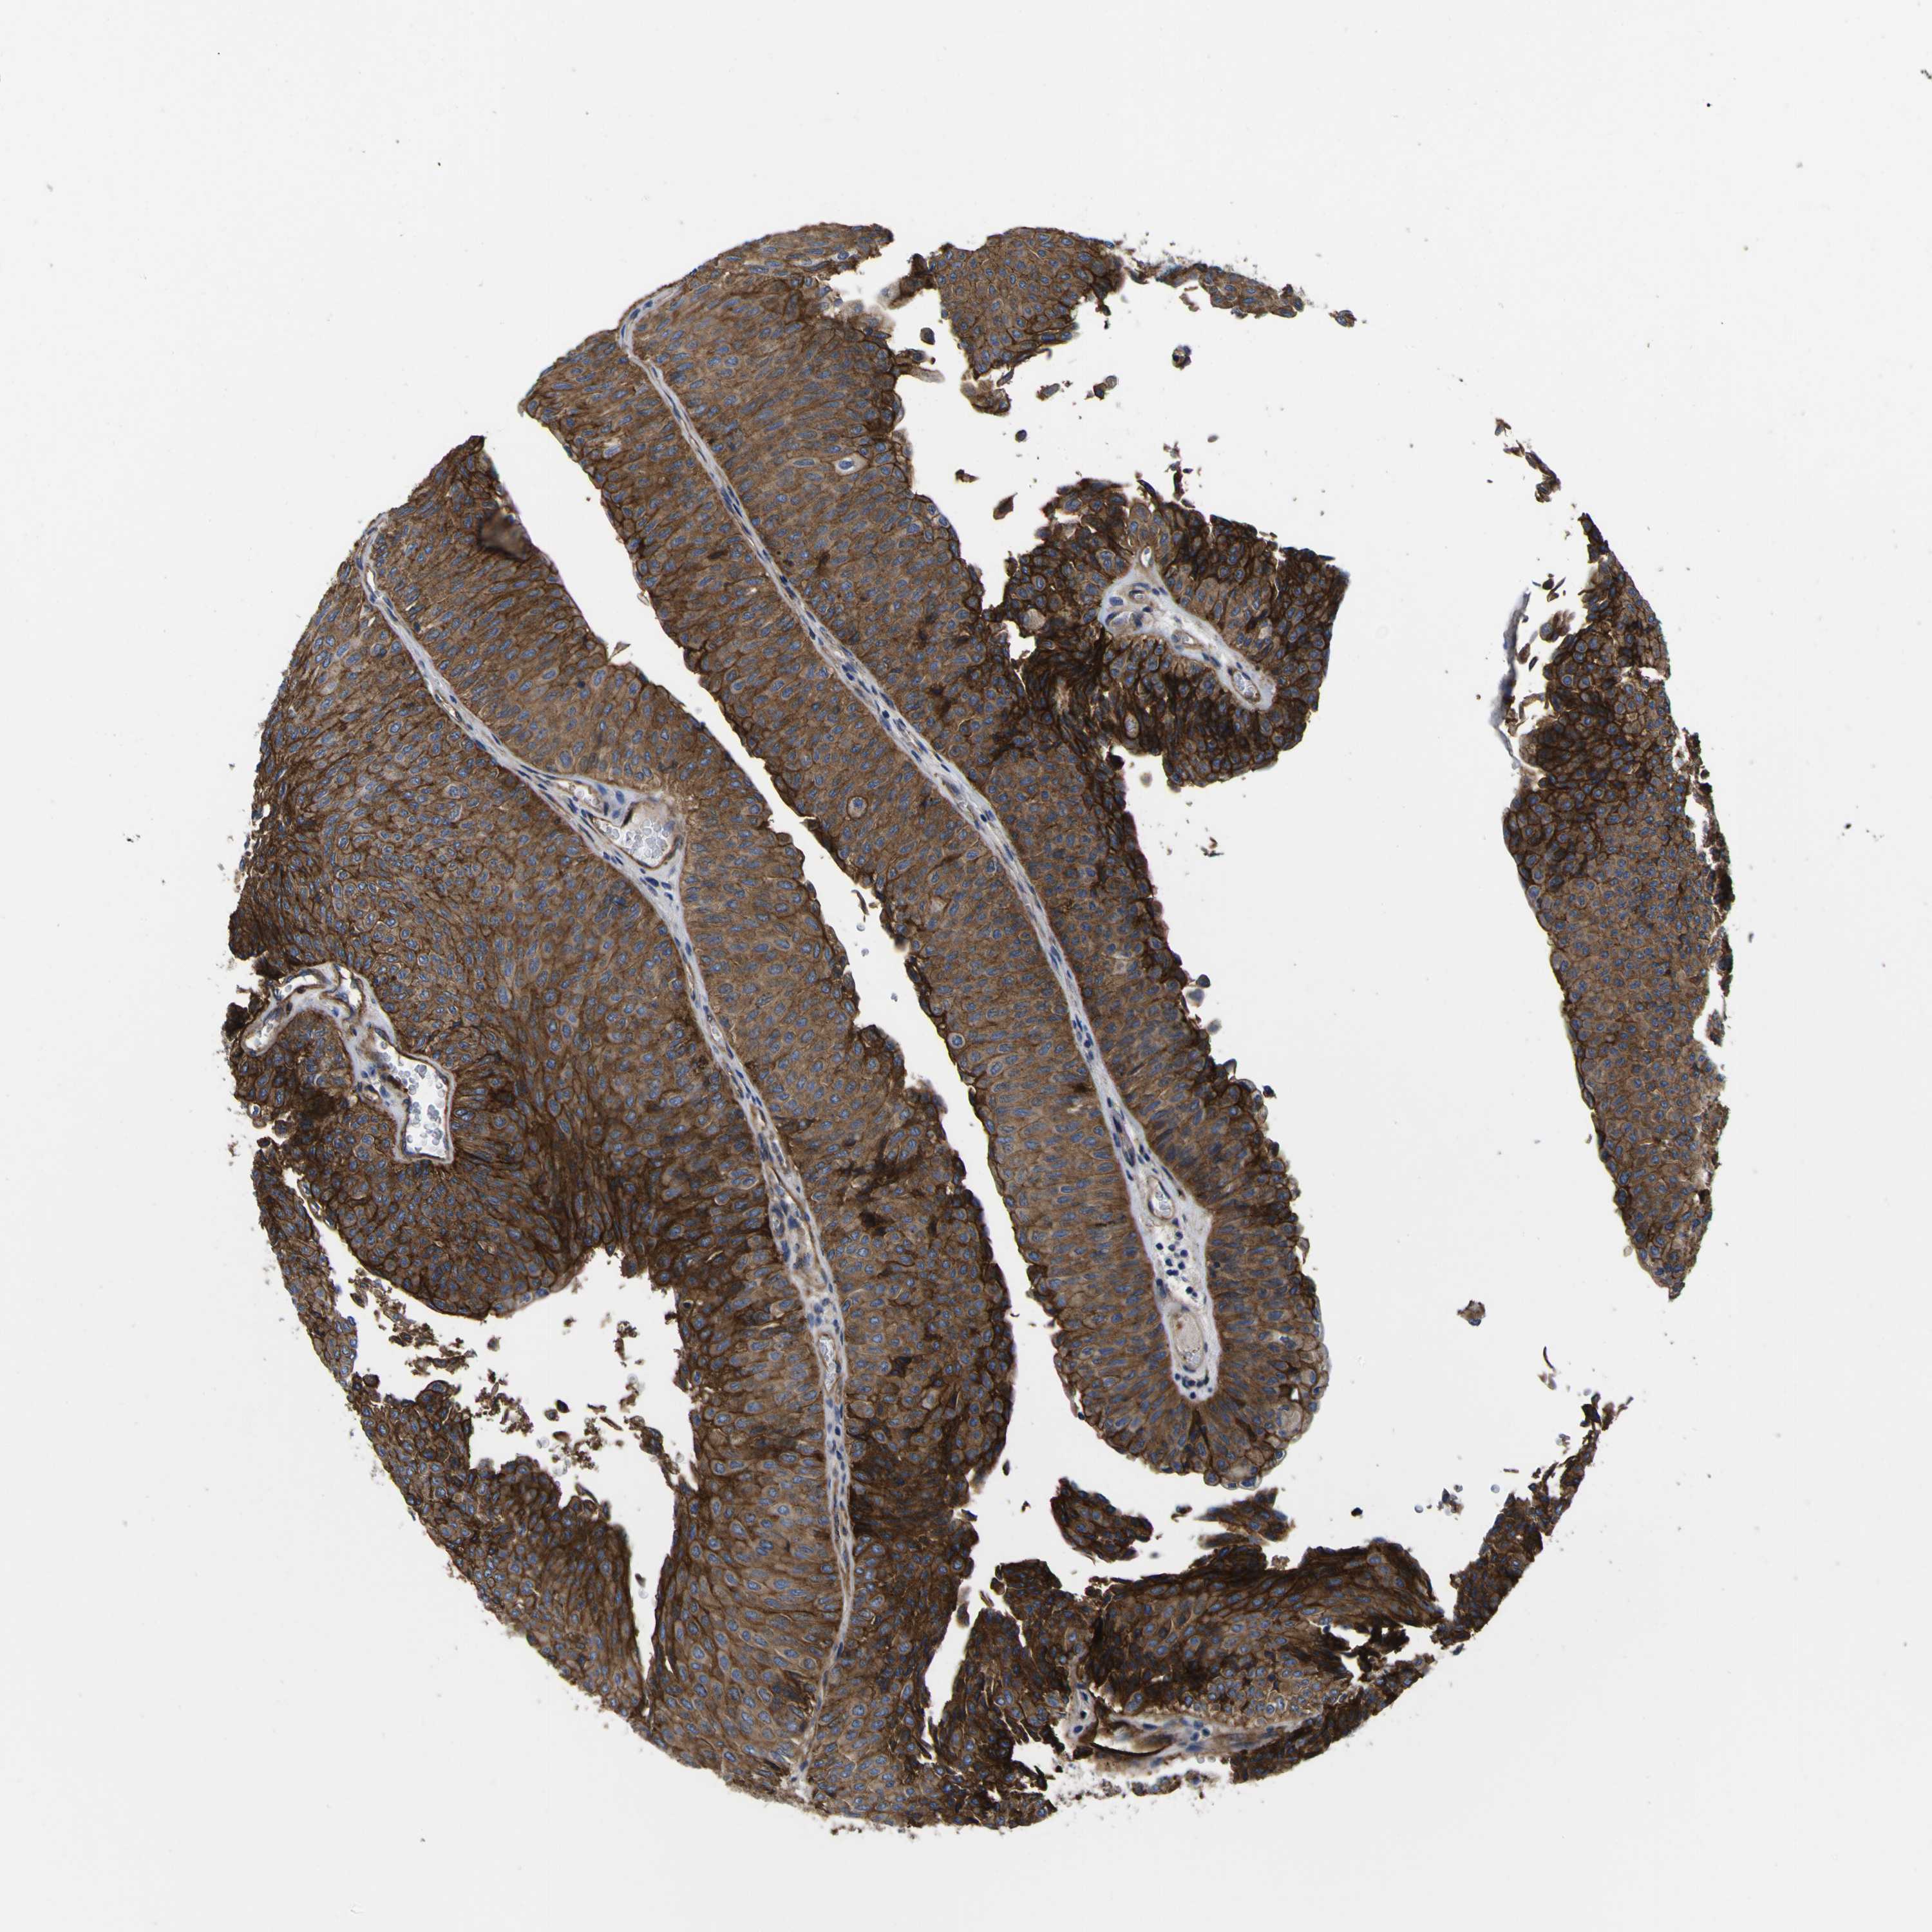

UROTHELIAL CANCER - Protein expressioni

A mouse-over function shows sample information and annotation data. Click on an image to view it in a full screen mode. Samples can be filtered based on level of antibody staining by selecting one or several of the following categories: high, medium, low and not detected. The assay and annotation is described here.

Note that samples used for immunohistochemistry by the Human Protein Atlas do not correspond to samples in the TCGA dataset.

Antibody stainingi

Antibody staining in the annotated cell types in the current human tissue is reported as not detected, low, medium, or high, based on conventional immunohistochemistry profiling in selected tissues. This score is based on the combination of the staining intensity and fraction of stained cells.

Each image is clickable and will lead to virtual microscopy that enables deeper exploration of all samples and also displays staining intensity scores, fraction scores and subcellular localization as well as patient and tissue information for each sample.

Antibody HPA011906

Antibody CAB002428

Urothelial carcinoma, Low grade

Urothelial carcinoma, High grade

Adenocarcinoma, NOS